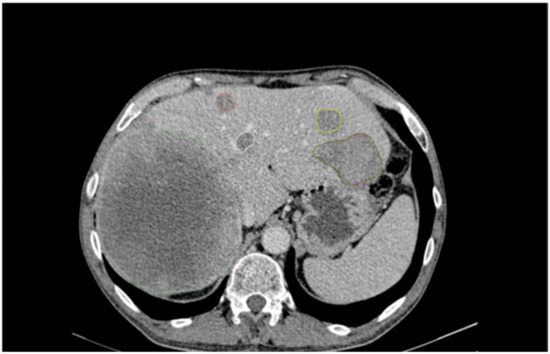

2.2. Image Analysis and Segmentation